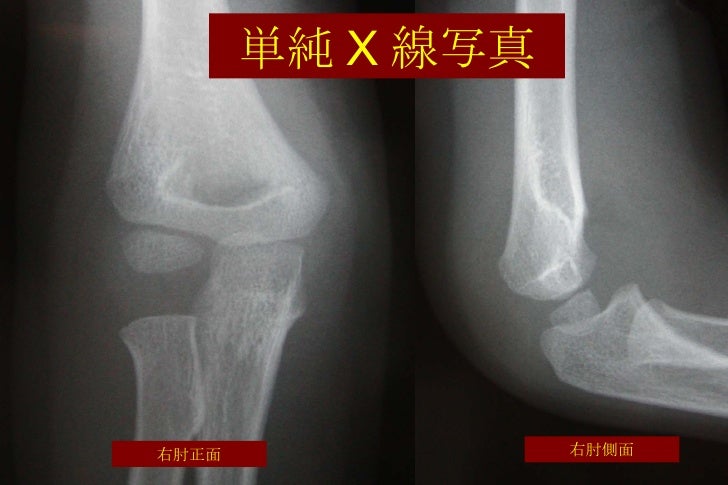

そのような特徴に加え、小児の骨の端の方は軟骨部分が多く、レントゲンに映りにくいという特徴もあります。 この症例は小児整形外科に精通していない医師は肩鎖関節脱臼と誤診してしまう可能性が非常に高いという意味で、 子どもは大人の縮小版ではない! という小児を扱う上での重要なことを再認識させてくれます。 前回の肘の上腕骨遠位骨端離開と同様、小児整形外科の真髄のような重要レントゲンでの検査は、骨折の型や転位方向を確認します。 転位が大きい場合、診断は容易です。 しかし転位の少ない場合は肘内障や外・内顆骨折との鑑別が難しいです。 4.上腕骨顆上骨折の一般的な治療 小児の顆上骨折では保存療法を第一選択とします。 保存療法が無効な場合は手術を選択します。 4-1.保存療法 整復 整復の際には他の組織損傷や神経循環障害の発生を予防するため愛護的に行 肘は明らかに変形しております。 その変形の形から即座に脱臼を疑い、レントゲン撮影を行いました。 これです。 間違いなく脱臼ですね。 しかも橈骨頭の近くに小骨片が見られますので、小さな剥離骨片を伴う、厳密に言えば脱臼骨折です。

とある小児整形外科医のつぶやき 肘関節を脱臼した13歳の少年のお話